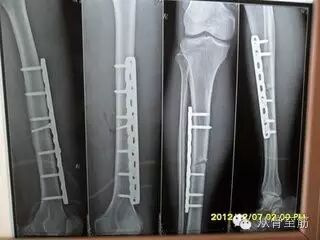

钢板一定要取出吗?

现在内固定物多为钛合金材料,排异性很小,理论上讲可以不取。老外是一般不取的,一是因为保险不报销,二是老外认为这不是个事。中国人则不然,总觉得身体里多个异物是个心病,所以很多人最终还是取出 了内固定。其实想一想很多革命前辈在身体里有很多弹片,一辈子没取也没事。咱们的钢板可比弹片高级多了。

手术后什么时间取出合适?一般下肢负重部位在术后骨折线消失1年半-2年取出较为合适,上肢一般在术后骨折线消失1年取出较为合适,如果想取出内固定,比上述时间晚一些没关系。但不能早,取早了容易再骨折;也不能太晚,超过3-5年则取出困难。再加上国内的器械公司多不能长久,很有可能5年以后当时提供钢板的公司已经消失了。